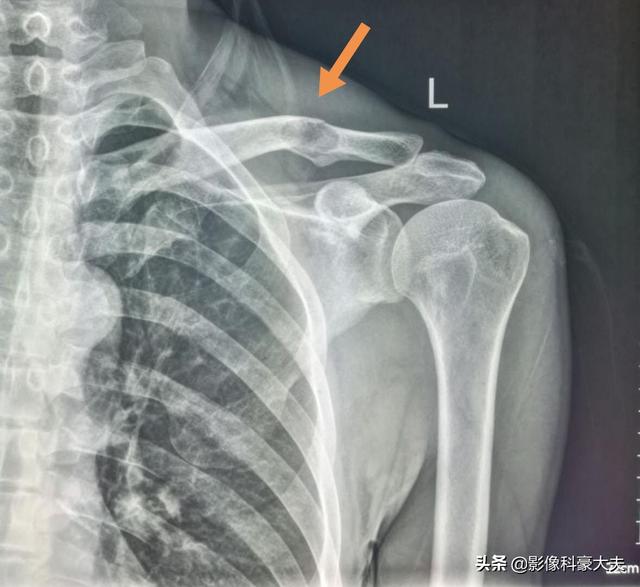

この症例は58歳のゲイ男性で、肩を軽く伸ばしただけで痛みが続くようになり、X線検査で低密度病巣が見つかった:

これは骨転移に基づく軽微な外力による病的骨折であった。穿刺が行われ、病理結果は低分化肺腺癌の骨転移であった。

左肺にあるこの不規則な結節が原発巣で、わずか2.6cmしかない。このような骨転移を伴う肺がんは、もはや手術不可能です。肺がんはあまりにもありふれた病気であり、初期症状の中には非典型的なものや無症状のものさえあるからだ。肺がんの約30%では、転移の症状が最初の症状であり、さらなる肺がんが発見される前に転移が最初に発見される。